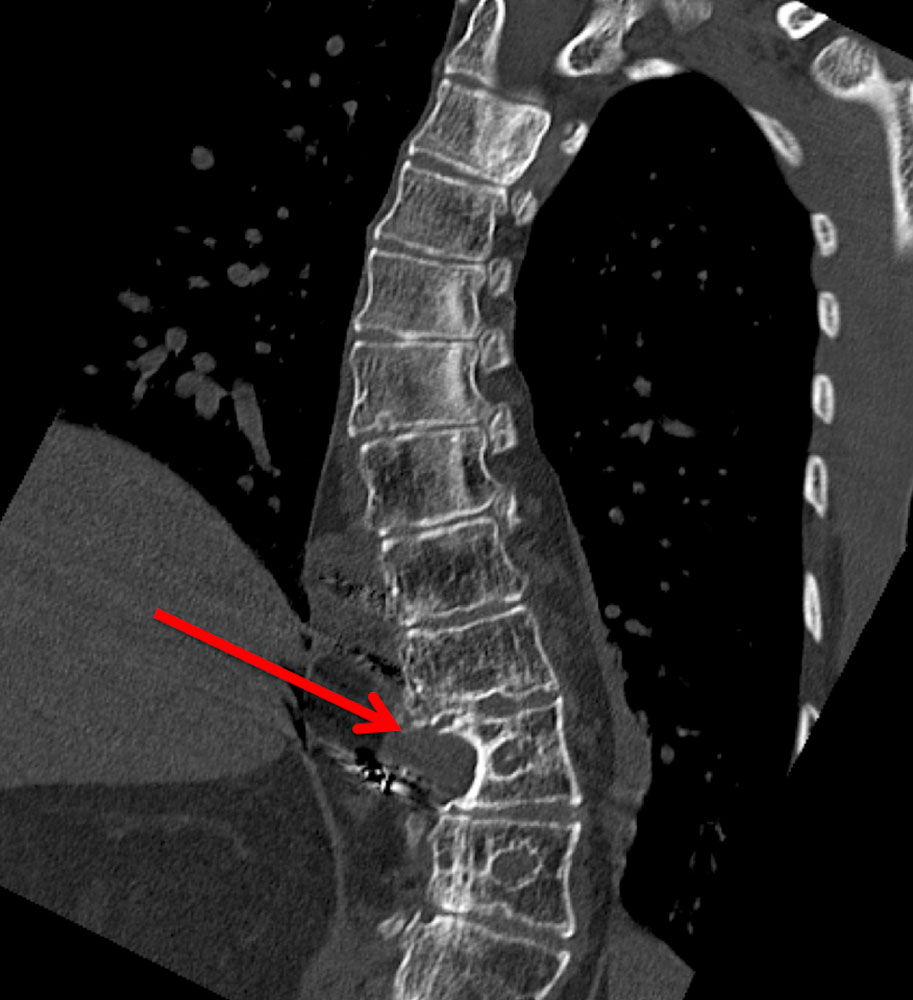

In patients with vascular anomalies, diagnosis of scoliosis should usually be further evaluated by MR imaging of the spine to distinguish whether the spinal curvature is due to a vascular malformation in the spine itself (e.g., in CLOVES syndrome) or a possible leg length discrepancy. On the other hand, it may be an idiopathic scoliosis that is present in the patient independently of the vascular malformation.

In addition, the vertebral bodies themselves or their immediate surroundings are sometimes involved in the vascular malformation in terms of pathological vessels. This complicates surgical treatment of scoliosis considerably and requires prior interventional repair of these vessels (e.g., by sclerotherapy or embolization).